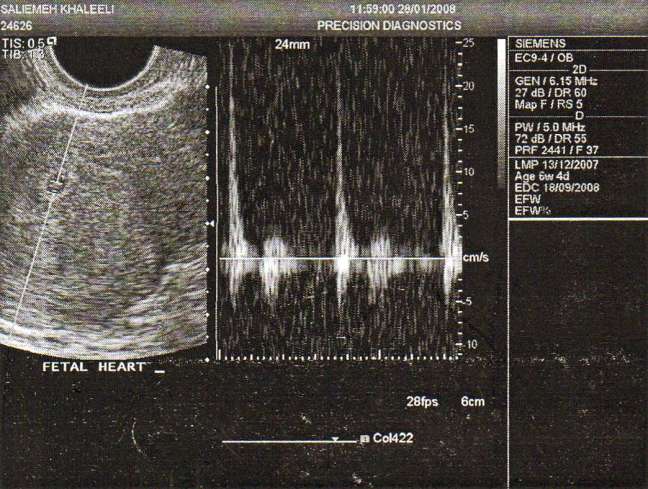

From Bombay we went to Delhi, and then back to Bangalore. My husband was arriving and we were to head out to Madras via road or did we fly I cannot remember. Everyone was happy with the news, I was too but not all the time. We drove to Pondicherry, and that was a long drive. We stopped at some fort by the beach, and saw that they had just found a woman who had drowned. What a horrible sight, and what was worse they just dumped her body in the trunk of the car and shut the trunk lid. We moved on and I decided to climb a wall to get sight of the view. Climbing down I had help and then decided to jump. My mom told me not to but it was too late. That night the inevitable happened I started bleeding and had to wait all night to get to the doctor the next day. OMG, her heart was beating, weak, but beating. I cried and asked for my husband to come in, but India has some weird rules and he could not hear the heartbeat. I cried and pleaded as I knew this was the only time I would hear that heart but they could not care less.

My husband had to leave on the day I had my ultrasound in Bangalore. The treatment of women who are about to lose their baby is horrendous in India. The lack of empathy and emotion really bothered me, like this life did not matter.They did the ultrasound and I was told “its dead”. I lay there motionless and without any emotion. Came out to a room full of people, looked at my mom and said the same thing-its dead. I was given the abortion pills and instructions. I just wanted someone to hold me, and I was alone, like I always was. My baby was no more, and my heart was broken never ever to be the same again. I was not going to be the same. My bitterness increased to a new level. I still had my smile, but no one knew the pain I was going through and I decided to shut the world out of my life.